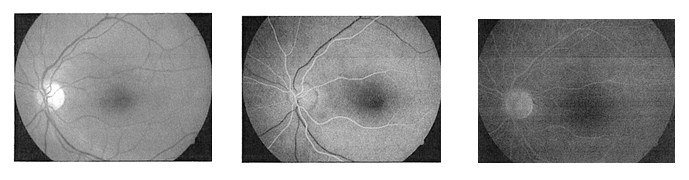

Badanie AF trwa zazwyczaj od 1 do 2 godzin. Przed rozpoczęciem badania do worka spojówkowego są wprowadzane krople, które rozszerzają źrenice. Następnie Pacjent siada przed aparatem do robienia zdjęć (tzw. funduscamera). Twarz przylega do mocowań tak, by głowa nie mogła się poruszać. W trakcie badania należy patrzeć przed siebie bądź w kierunku określonym przez znacznik. W pewnym momencie do żyły jest aplikowany kontrast. Następnie wykonuje się serię zdjęć co określony czas. Dzięki podanemu wcześniej środkowi kontrastowemu na zdjęciach można dostrzec białe unaczynienie oka, wyraźnie odznaczające się na czarnym tle. Badanie trwa od 1,5h do 2h.